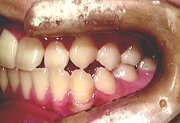

症例4 歯列矯正